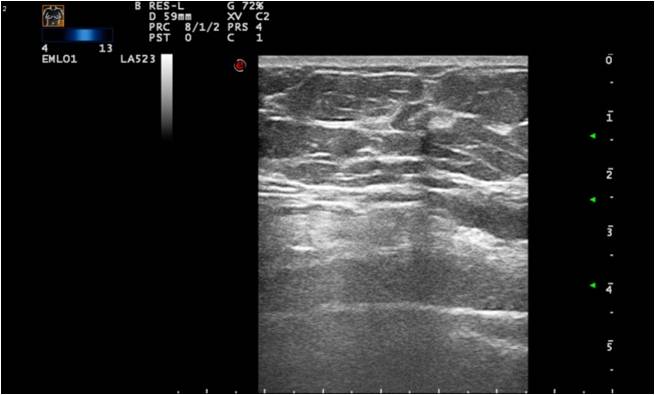

12.2.2.2. Breast Ultrasonography:

The examination is started with ultrasound under the age of 30. For women above 35 years of age it is the complimentary examination of mammography, while for women of 30-35 years we choose the first modality depending on the symptoms of the patient. In breasts of greater volume, mammography couldn’t be skipped.US is used as primary examination during pregnancy and lactation, as well as in patients with acute phase inflammatory processes.

Technical requirements: a high resolution linear head of 7.5 MHz, with a maximum length of 4-5 cm. A second supplementary head of 12-18 MHz is also recommended. The examination needs to be archived.

Diagnostic indications:

• separation of solid and cystic lesions

• examination of locoregional lymphnodes

• examination of chest wall

• detection of recidive tumour

• controll of benign lesions

• guidance of sampling

Ultrasonography can help in their differentiation; can depict anechoic cystic lesions (Picture17.) or solid masses (Picture 18.). These lesions usually each have a smooth, sharp edge and echo-enhancement can appear behind them. Rarely, cysts contain tumors. (Picture19.).

Ill-defined margins, with uneven contours and blurred edges are usually characteristic of malignant lesions. During ultrasound examination echo-attenuation occurs frequently behind these inhomogeneous hypo-echogenic masses (Picture 20).